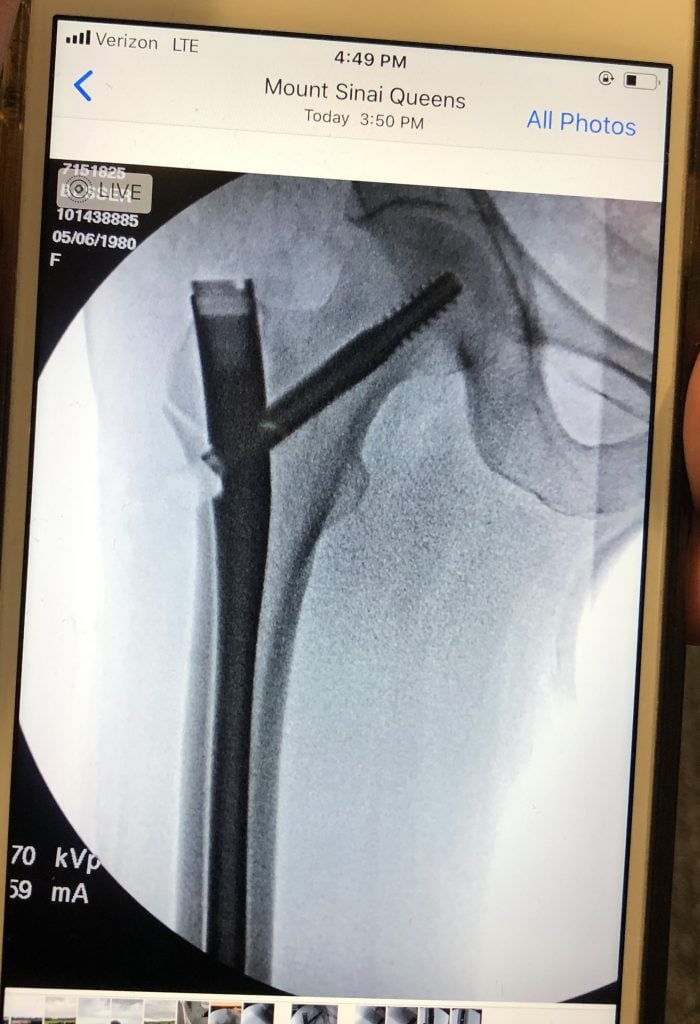

I started working with Dr. Goolsby and Dr. Serota in 2018 when I got a stress fracture in my left hip while training for the 2018 NYC Marathon. I was then diagnosed with osteoporosis and the injury took an abnormally long time to heal because of this. They got me running again and in 2019 I was PRing in every race that I did and had amazing training going into the 2019 NYC Marathon where I hopped to BQ. My dreams were cut way short when my right hip and femur spontaneously broke at Mile 14 of the race and I was taken off the course in an ambulance. I spent 5 days in a Queens hospital and have a metal rod in that right leg/hip. One of the first things I did in that ER on Sunday Nov 4, 2019 was reach out to Dr. Goolsby, who picked up on a Sunday, to seek her advice and start the wheels turning to come under her care because I trusted her completely. After months of rehab and working with Dr. Serota and Dr. Goolsby to improve my bone health, treat my RED syndrome, and heal my hip I was able to slowly resume running in the summer of 2020. After another setback in the spring of 2021, we determined my bones weren't yet ready to marathon. But after 3 long years and 3 days since I first was taken off the marathon course, I was able to complete the 2022 Marathon on Nov 6.